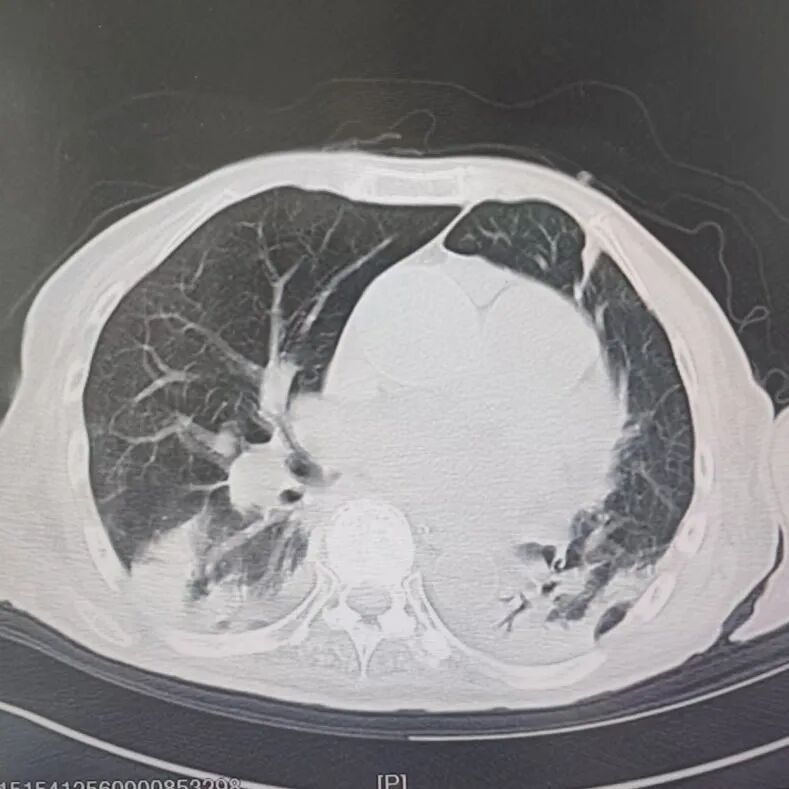

引言 / / Introduction 年近8旬的陈阿姨(化名)因脑梗长期瘫痪在床,康复期间突然高烧不退,体温升至39℃,在抗感染过程中,她并发高渗性脱水,病情急剧恶化,被紧急送入ICU。此时,她已气管切开,依靠呼吸机维持呼吸,并伴有低蛋白血症、低钾高钠血症及房颤等多种危重情况,命悬一线! PART. 01 多重泛耐药菌叠加大量基础病 治疗陷入“死胡同” 呼吸与危重症医学科及ICU通力协作,稳住患者生命体征。治疗过程中,进一步的病原学检查结果令人心惊:陈阿姨的肺部遭遇多种“超级细菌”混合侵袭,包括铜绿假单胞菌、鲍曼不动杆菌、嗜麦芽窄食单胞菌、金黄色葡萄球菌、木糖氧化无色杆菌、粘质沙雷菌等高度耐药菌,堪称耐药菌“大本营”。这些细菌对常用抗生素几乎全部耐药,治疗难度高,死亡率高。 治疗前患者肺部影像 PART. 02 多学科强强联手 量身定制攻坚方案 面对无药可用的困境,呼吸科没有放弃!宋刚主任带领团队联合药学部、检验科、重症医学科成立多学科治疗组,根据患者身体情况实时调整用药,逐一攻破耐药菌。这场与“超级细菌”的拉锯战持续了30多个日夜。 在医护日夜坚守和家属全力配合下,陈阿姨的感染终于被遏制:高烧退了,肺部阴影消散了!就在即将宣告胜利时,又发现她存在泌尿感染问题,随即转入泌尿外科协同治疗。当宋主任回访时,看到陈阿姨精神焕发、体温平稳,所有参与救治的人都感慨万分!这场救治,正是呼吸与危重症医学科攻坚耐药菌硬实力的生动体现! 治疗后患者肺部影像 从“无药可用”到“绝处逢生”,此次成功救治,集中体现了呼吸与危重症医学科以耐药菌精准诊治为核心的学科特色与技术优势。面对一次次的严峻挑战,科室始终秉持“生命至上、知难而进”的信念,以多学科协作为平台,凭借个体化精准用药策略,为患者寻找生机,为更多陷入困境的患者和家庭带去了实实在在的希望。 PART. 03 人民医院 人民名医 宋刚 主任医师 ·葫芦岛市第二人民医院呼吸与危重症医学科主任 ·辽宁省生命科学学会东北呼吸与危重症医学(PCCM)分会辽宁省基层委员会副主任委员 ·辽宁省细胞生物学学会放射粒子治疗专业委员会理事 ·辽宁省抗击新冠肺炎疫情先进个人 ·葫芦岛市劳动鉴定委员会专家库成员 ·葫芦岛市医学会呼吸内科学分会第三届委员会副主任委员 专业特色:擅长呼吸系统疑难及急危重患者的救治,如急慢性支气管炎、支气管哮喘、慢性阻塞性肺疾病、肺炎、肺栓塞、肺癌、间质性肺疾病、睡眠呼吸暂停综合征等,尤其擅长有创无创机械通气、支气管镜下相关检查及治疗(TBNA、气道支架置入术、球囊扩张等)、全肺灌洗术等领先技术,发表国家级期刊多篇。